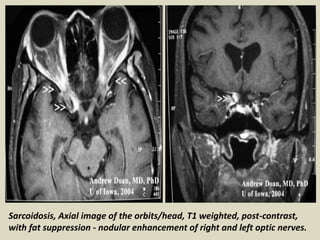

Cranial nerve involvement: Cranial nerves are affected in up to 50% of patients with

neurosarcoidosis. There is poor correlation between imaging findings and clinical

symptoms. While facial nerve deficits are most commonly found clinically, the optic nerve is

the most common cranial nerve to appear abnormal on MRI. Affected cranial nerves show

enhancement and thickening with or without associated leptomeningeal involvement.

Optic nerve sarcoidosis.

Sarcoidosis, Axial image of the orbits/head, T1 weighted, post-contrast,

with fat suppression - nodular enhancement of right and left optic nerves.